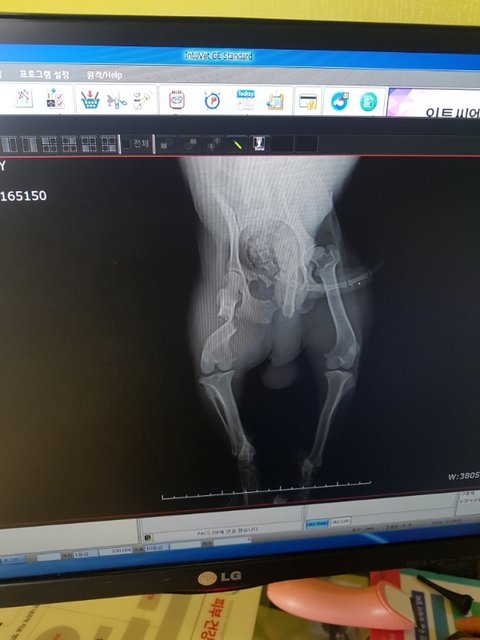

뒷다리골절과 사상충

뒷다리골절 덜렁거리는 다리로 꼬리를 흔들며 다가와 눈을 맞추던 아이..

눈속에 많은것을 담고 있던 아이를 능력이 안되지만 고통속에 둘수없어 병원으로 이동했습니다

대퇴부골절...

그리고 심한 사상충...

골절도 골절이지만 성충이 어마어마하게 많아 충을 꺼내는 수술을 해야할정도라고 합니다